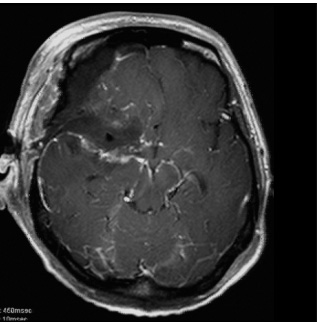

症例4は58歳。顔面の違和感で発見された小脳橋角部、テント髄膜腫である。三叉神経や外転神経、滑車神経などを巻き込む腫瘍。脳幹圧迫も強く症状は軽微であったが、腫瘍摘出を行った。後方複合錐体アプローチで一期的に神経を温存して腫瘍を摘出した。一時的に滑車神経麻痺による下方を見た時の副視が出現したが、改善している。

術前MRI 右側の脳神経を巻き込む腫瘍

神経を温存し腫瘍摘出